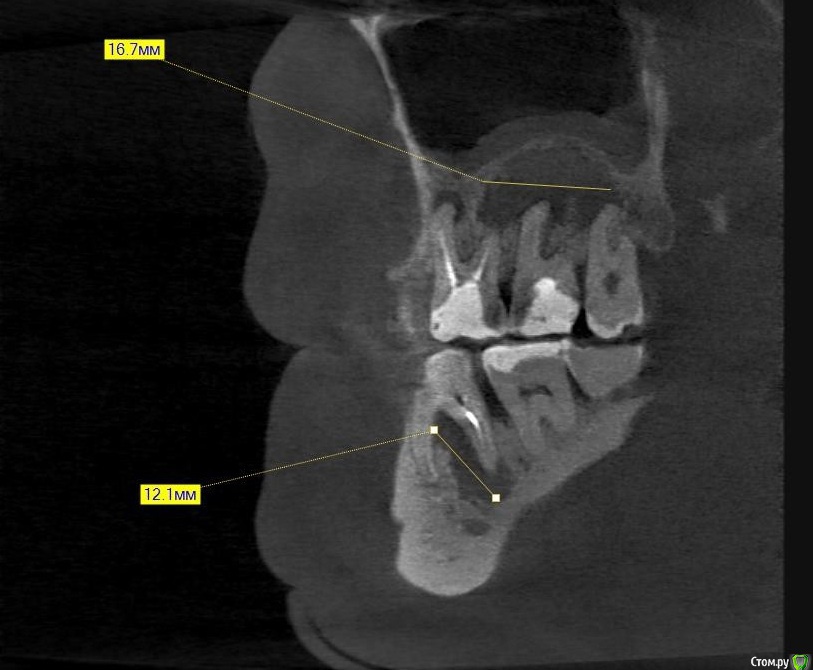

Hans85 Опубликовано 14 января, 2015 Автор Поделиться Опубликовано 14 января, 2015 Полагаю на КТ будет не такая уж радужная картинка...Чем завершено лечение? Коронка?Наконец то пациент пришел на коронку.Вот и Кт ,да заживление не 100% ,но все же . 3 Ссылка на комментарий